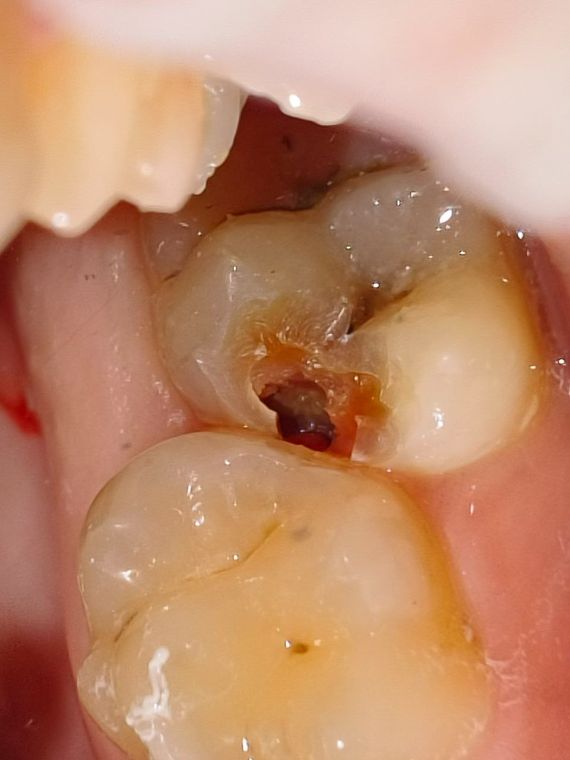

Во время лечения

Как видно после "встрытия" зуба, ткани внутри более темного цвета и изменены по структуре. Дентин мягкий легко убирается инструментом

окрашивание

Окрашивание специальным индикатором "Кариес-индикатор" показывает зоны поражаения ярко малиновым цветом. Такие ткани необходимо убирать.

Мягкий дентин

Так же на фото можно увидить "комочки" тканей мягкой консистенции - это CID дентин. То есть ткани инфицированные кариесом.